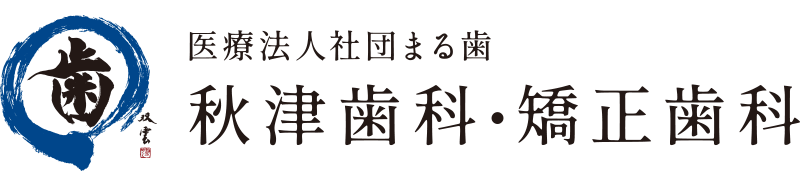

レントゲン写真

顎関節の形態が左右非対称ですが、機能に異常は認められませんでした。

下の歯は虫歯があり、グラグラな状態でしたが、上顎の歯は揺れは認められませんでした。

下顎の歯ぐきは細く、痩せていたため、強い力では噛みにくいことが考えられました。